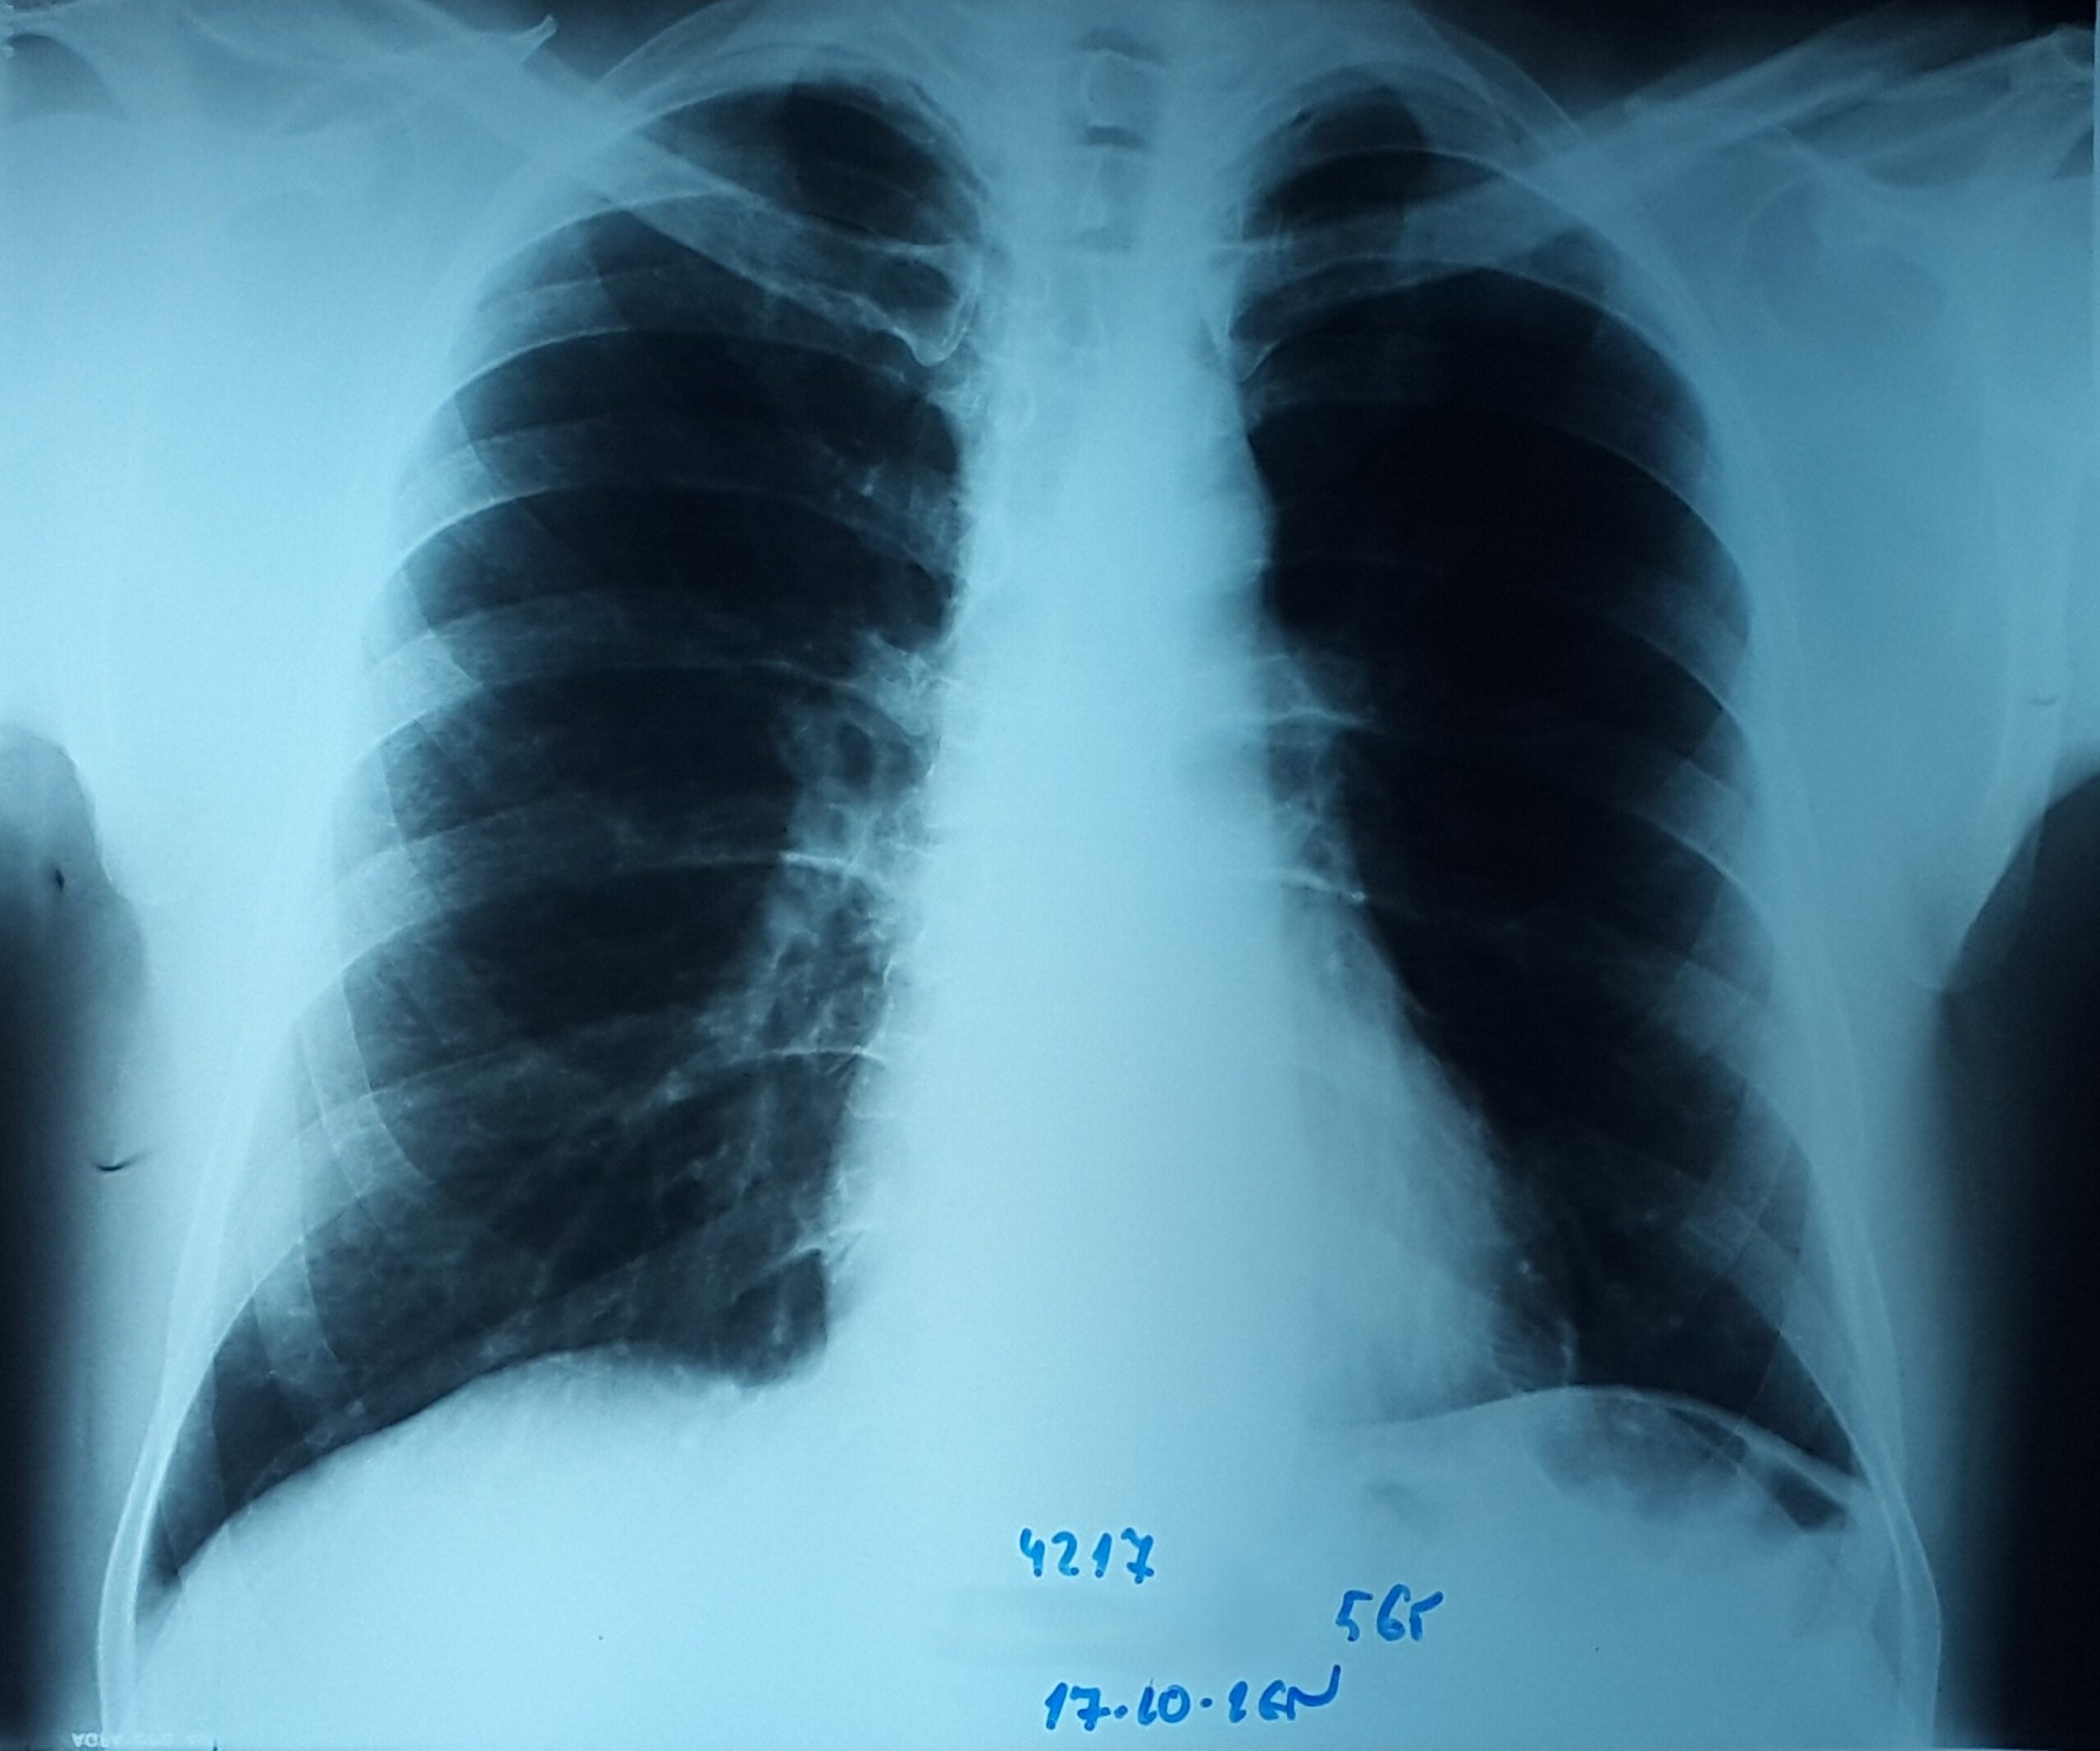

- გულმკერდის რენტგენოგრაფია რეზექციიდან 1 წელში

მარცხენა ფილტვი სრულად გაშლილია.